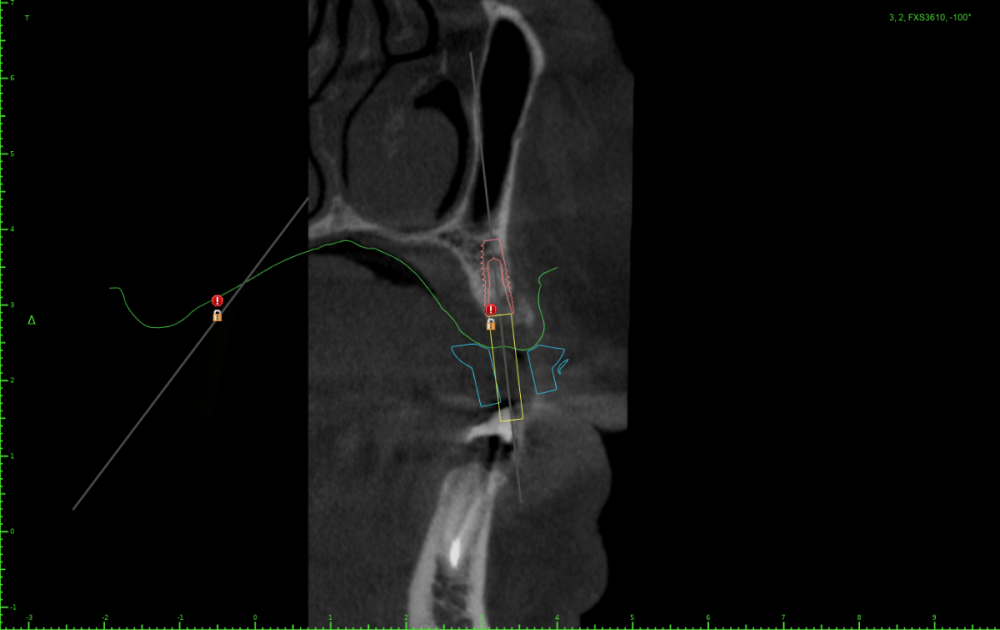

АнтонТЛТ Опубликовано 25 июля, 2023 Поделиться Опубликовано 25 июля, 2023 Значит пора выложить скрины проекта шаблона) посмотреть что там с параллельностью, если там всё параллельно, тогда искать причину почему имплантаты завалены Ссылка на комментарий

Женька Опубликовано 25 июля, 2023 Автор Поделиться Опубликовано 25 июля, 2023 23 часа назад, Женька сказал: Но буду честен, можно было чутка 1.4 наклонить и сооснопоставить. я же уже говорил об этом. Вот если бы параллелил по 1.6 . Как по мне так себе позиция Поэтому выбрана такая И соответственно если бы параллелил по 1.4 Ссылка на комментарий

АнтонТЛТ Опубликовано 25 июля, 2023 Поделиться Опубликовано 25 июля, 2023 А сагиттальный срез? Ссылка на комментарий

АнтонТЛТ Опубликовано 25 июля, 2023 Поделиться Опубликовано 25 июля, 2023 По фото выглядит так как будто установлены так Ссылка на комментарий

Женька Опубликовано 26 июля, 2023 Автор Поделиться Опубликовано 26 июля, 2023 (изменено) @АнтонТЛТ , не, не делали. Через полгодика сделаю, как раз пластика с другой стороны (сетка, которую выкладывал) должна созреть.) Возможно из-за синуса ось сместилась ну и были определённые проблемы привязки КТ и скана. Зубы есть, но программа не хотела даже по точкам сопоставлять. Пришлось в ручную. саггиталь не могу выстроить как не кручу, чтобы оба болта попали. Изменено 26 июля, 2023 пользователем Женька Ссылка на комментарий